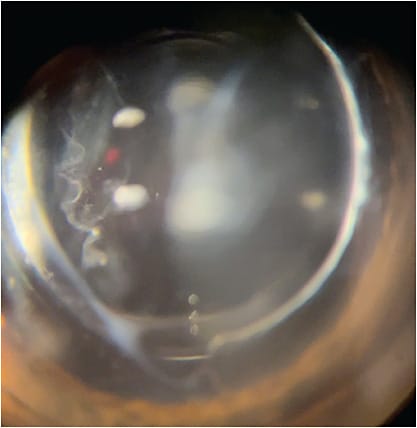

Before any intervention, surgeons should confirm the diagnosis by evaluating the patient’s subjective complaints, as well as objective exam findings. Floaters can be difficult to quantify objectively, as the patient may present with 20/20 visual acuity but complain of generalized blurred vision. The key is to ascertain whether patients see a “film” or “fog” moving across their vision. Often, they will describe their vision as fluctuating in nature, and their vision may “clear up” as the opacity moves out of their central vision with their eyes’ changing gaze. Some patients will also describe seeing “cobwebs”, “strings”, or “strands” within their vision. On slit-lamp examination, VOs can be visualized in the anterior vitreous space as dense syneresis, veils, or strands, similar to the patients’ subjective descriptions. They can also be visualized and grossly quantified on optical coherence tomography, ultrasound, and fundus photography. Contrast sensitivity testing can be used to more objectively assess its visual impact and as a tool to quantify improvement following treatment.